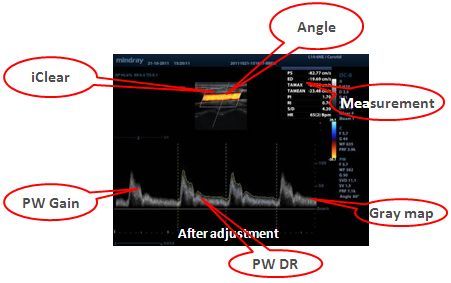

iClearTM

–ü–æ–∑–≤–æ–ª—è–µ—Ç —É–ª—É—á—à–∏—Ç—å –∫–∞—á–µ—Å—Ç–≤–æ –∏–∑–æ–±—Ä–∞–∂–µ–Ω–∏—è, –æ—Å–Ω–æ–≤—ã–≤–∞—è—Å—å –Ω–∞ –∞–≤—Ç–æ–º–∞—Ç–∏—á–µ—Å–∫–æ–º —Ä–∞—Å–ø–æ–∑–Ω–∞–≤–∞–Ω–∏–∏ —Å—Ç—Ä—É–∫—Ç—É—Ä.

iTouchTM

–ü–æ–∑–≤–æ–ª—è–µ—Ç –≤—ã–ø–æ–ª–Ω—è—Ç—å –º–≥–Ω–æ–≤–µ–Ω–Ω—É—é –∞–≤—Ç–æ–º–∞—Ç–∏—á–µ—Å–∫—É—é –æ–ø—Ç–∏–º–∏–∑–∞—Ü–∏—é –∏–∑–æ–±—Ä–∞–∂–µ–Ω–∏—è –≤ —Ä–µ–∂–∏–º–∞—Ö –í, –ø—Ä–∏ —Ü–≤–µ—Ç–æ–≤–æ–º –∏ –∏–º–ø—É–ª—å—Å–Ω–æ-–≤–æ–ª–Ω–æ–≤–æ–º –¥–æ–ø–ø–ª–µ—Ä–µ (PW) –Ω–∞–∂–∞—Ç–∏–µ–º –æ–¥–Ω–æ–π –∫–ª–∞–≤–∏—à–∏.